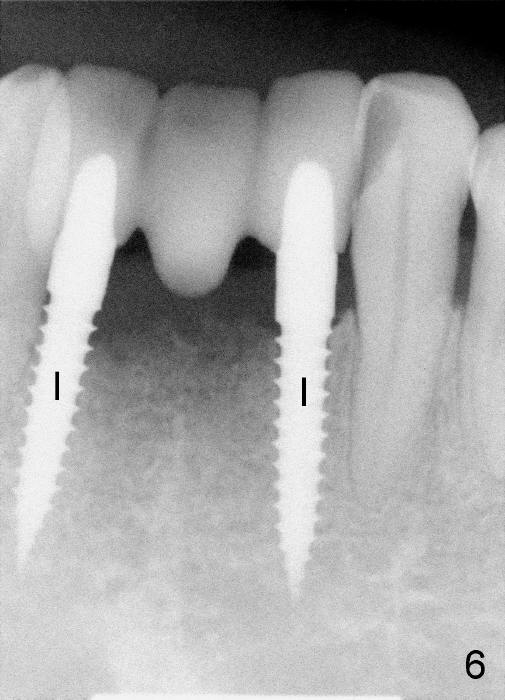

A sixty-eight-year-old lady wants to have fixed prosthesis for missing lower incisors (Fig.1).

Fig.2 is an axial section at crest level.  The buccolingual width is about 4 mm.  The two red circles represent two 3-mm implants placed at the sites of #23 and #26.

Fig.3 and 4 are sagittal sections for the sites of #23 and 26, respectively.  The widths of the crest are 3.8 and 3.3 mm, respectively.  The height is more than 15 mm.